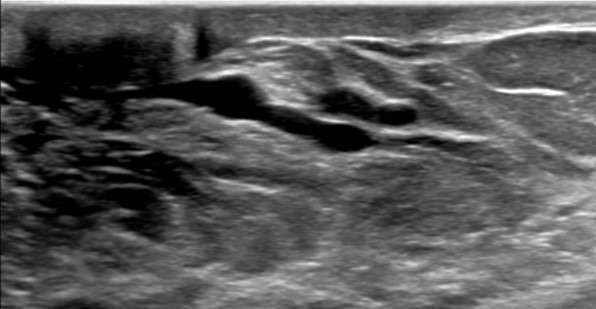

Ultrasound features include:

- Hypoechoic tubular structures measuring larger than 2 mm in diameter or 3 mm in diameter at the ampulla. These dilated ducts may be exhibit anechoic intraductal features secondary to simple fluid or low-level internal echoes secondary to intraductal debris.

- Inflammatory changes around the ducts, such as hypoechoic halo or echogenic strands, can be observed on ultrasound.